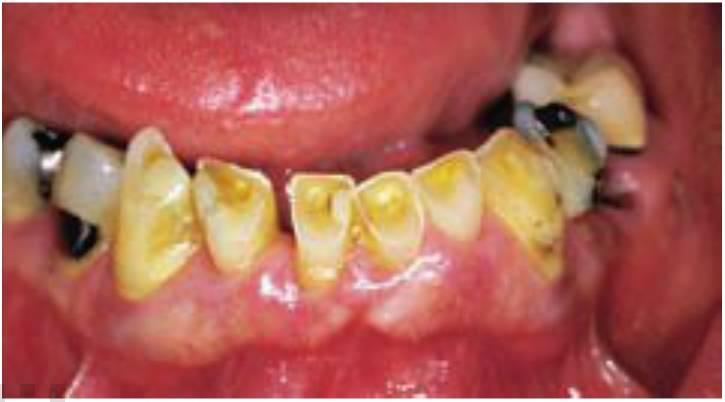

Afortunadamente, existen muchos signos clínicos que avisan de un excesivo rechinamiento. Los signos del bruxismo incluyen un aumento del tamaño de los músculos masetero y temporal (estos músculos y el pterigoideo externo pueden presentar molestias), desviación del maxilar inferior en la apertura, disminución de la apertura oclusal, aumento de la movilidad dentaria, desgaste cervical de los dientes, fractura dentaria o de las restauraciones y descementado de coronas o de prótesis fija. Sin embargo, el método de diagnóstico mejor y más sencillo del bruxismo es el examen del desgaste dentario. No solo es la forma más fácil de determinar el bruxismo en cada paciente individual, sino que permite, además, clasificar esta patología en ausente, suave, moderada y grave (figs. 6-1 a 6-3). Si no existen patrones de desgaste anterior denota una ausencia de bruxismo. En el bruxismo suave aparece un ligero desgaste en dientes anteriores sin que exista un compromiso estético. El bruxismo moderado conlleva facetas de desgaste incisales obvias, pero no hay un patrón de desgaste oclusal posterior. En el bruxismo grave desaparece la guía anterior por el excesivo desgaste y, además, el desgaste dentario posterior es obvio.

A menudo, los pacientes bruxistas repiten movimientos mandibulares, diferentes a los movimientos bordeantes, y tienen una determinada dirección. Como resultado, el desgaste oclusal es muy específico y principalmente en un solo lado de la arcada, o incluso, en solo unos dientes (fig. 6-4).

Este patrón de engranaje normalmente continúa después del tratamiento. Si el dentista restaurador restablece la guía incisiva sobre los dientes que se han visto gravemente afectados por el patrón de engranaje bruxista, se aumentará la incidencia de complicaciones sobre esos dientes. Las complicaciones más frecuentes sobre los dientes restaurados con este «método de destrucción» son la fractura de la porcelana, descementación de prótesis y fractura radicular. Cuando los implantes soportan las coronas en el marco de esta senda de destrucción, el implante podrá fracasar, fracturarse o presentar una pérdida de hueso crestal, asimismo se puede perder el to millo del pilar, fracturar la porcelana o desprenderse las restauraciones. Si el paciente continúa con un patrón grave de bruxismo, la pregunta no sería si aparecerán complicaciones, sino cuándo y cuáles. El dentista debe avisar al paciente de que estos hábitos causan esos problemas. El tratamiento puede estar enfocado a reparar estos problemas, pero existirán complicaciones si no se reduce el bruxismo.